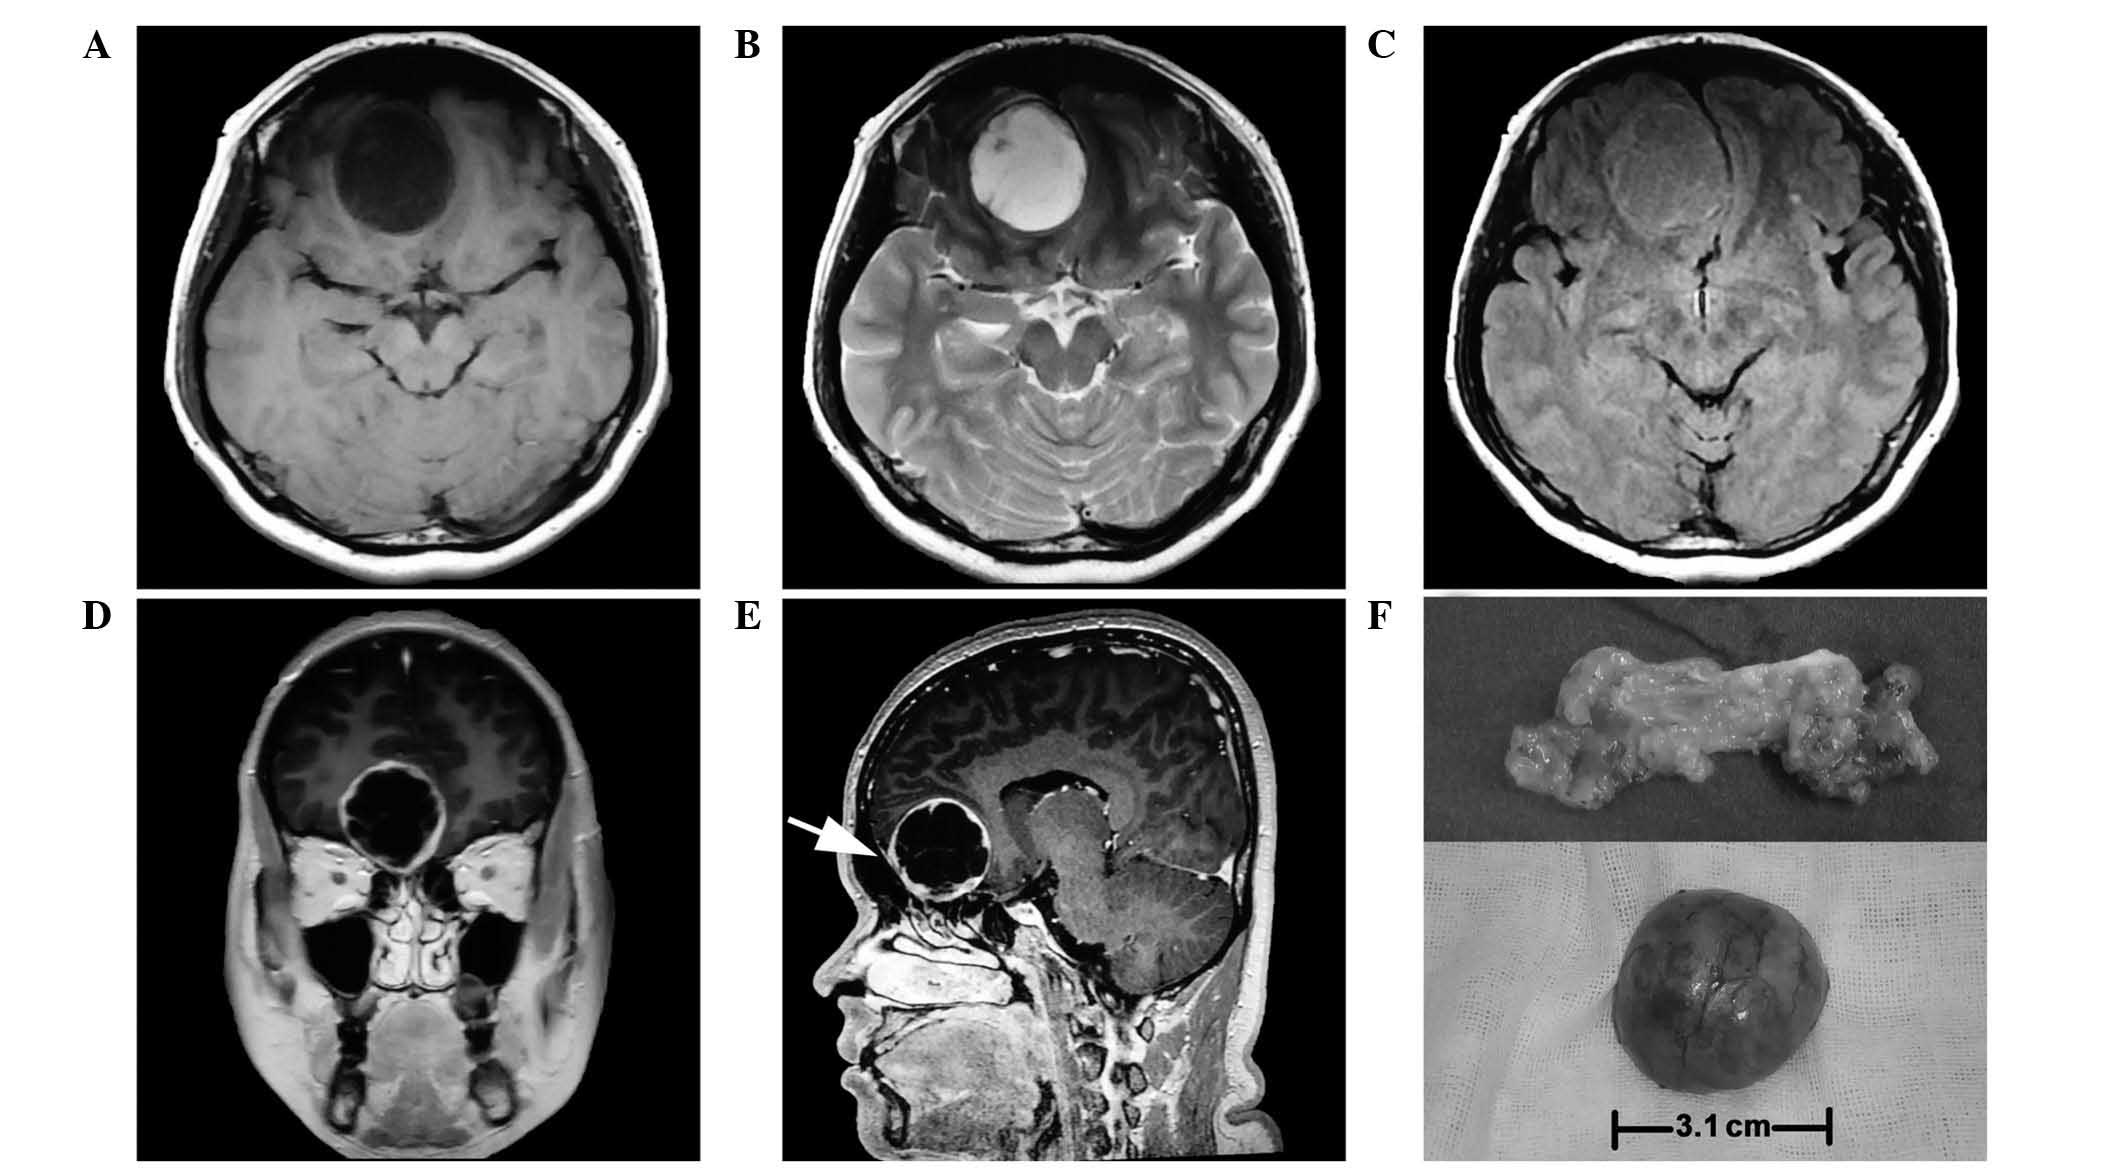

On March 10, 2014, a 34-year-old woman was admitted to The Second Affiliated Hospital of Dalian Medical University (Dalian, China) presenting with a history of hyposmia for 1 year, accompanied by a gradual dizziness and emotional lability for 2 months. No seizures, visual disorder, cerebrospinal fluid rhinorrhea or neurofibromatosis-related family history was recorded. Physical examination detected neither focal neurological deficits nor abnormal pigmentation of neurofibromatosis, with the exception of right hyposmia. Magnetic resonance imaging (MRI) scan (MR Signa 3.0T Excite; GE Healthcare Bio-Sciences, Pittsburgh, PA, USA) revealed a 3.0×3.0×3.1-cm extra-axial, globose, well-defined mass at the midline of the anterior cranial fossa, which deviated to the right. The tumor displayed homogeneous hypointensity on T1-weighted images, hyperintensity on T2-weighted images and isointensity on fluid-attenuated inversion recovery, and was shown to have caused brain parenchyma deformation without obvious peritumoral edema (Fig. 1A, B and C). Following the administration of intravenous gadolinium (Sigma-Aldrich, St. Louis, MO, USA), the tumor was heterogeneously enhanced and a peculiar membrane was observed inside the cystic wall. The tumor boundary appeared clear and smooth, while the main part was tightly connected to the endocranium (Fig. 1D and E).

Figure 1.

MRI of the brain. (A) Homogeneous hypointensity was observed on T1-weighted images (axial view). (B) Homogeneous hyperintensity was observed on T2-weighted images (axial view). (C) Homogeneous isointensity was observed on fluid-attenuated inversion recovery image (axial view). (D) Enhanced MRI on coronal view showing that the bone of the frontal base was slightly depressed toward the nasal cavity. (E) MRI scan showing that the basilar part of the tumor was tightly connected to the endocranium, mimicking dural tail sign on sagittal view (arrow). (F) Top: The tumor appeared fat-like inside upon dissection, as it was yellow and soft. Bottom: The tumor was covered by a smooth capsule. MRI, magnetic resonance imaging.

The patient underwent bifrontal craniotomy. When the right frontal lobe was softly lifted, a grayish red tumor with a glistening appearance was observed to be attached to the olfactory groove. The tumor was located in the intradural, extra-axial space, attached to the right anterior part of the cribriform plate. A large volume of a clear, non-congealable yellow liquid was extracted from inside the tumor. In addition, the right olfactory tract could not be identified, and the left olfactory tract had been squeezed by the tumor. The tumor was completely resected, and when dissected, it appeared to contain fat, as it was soft and yellow (Fig. 1F), however subsequent pathology revealed that fat was not present. The cribriform plate protruded slightly towards the nasal cavity; however, the bone cortex was intact. Using a microscope (MT4000D; Meiji Seika Kaisha, Ltd., Tokyo, Japan), the tumor tissue was examined histologically and the findings described a tumor composed of spindle cells, with an eosinophilic protoplasm and tadpole-shaped nucleus. No tumor necrosis or blood vessel hyperplasia was observed (Fig. 2A). Immunostaining results revealed positivity for S100 protein (polyclonal rabbit anti-human S100 antibody; cat. no. ENT4197; 1:10; Elabscience Biotechnology Co., Ltd, Wuhan, China) (Fig. 2B) and vimentin (polyclonal rabbit anti-human antibody; cat. no. ENT4879; 1:10; Elabscience Biotechnology Co., Ltd.) (Fig. 2C), and negativity for epithelial membrane antigen (monoclonal rat anti-human antibody; cat. no. BM0042; 1:10; Boster Inc., Wuhan, China) (Fig. 2D), glial fibrillary acidic protein (polyclonal chicken anti-mouse cat. no. ab4674; 1:10; Abcam, Cambridge, MA, USA) (Fig. 2E) and Leu-7 (monoclonal mouse anti-human antibody; cat. no. ab187274; 1:10; Abcam) (Fig. 2F). The Ki-67 (polyclonal rabbit anti-human antibody; cat. no. EPP14636; 1:10; Elabscience Biotechnology Co., Ltd.) index was 1% (Fig. 2G); therefore, the final pathological diagnosis was OECT. The postoperative course of the patient was uneventful, without adjuvant radiation and chemotherapy. No evidence of tumor recurrence was observed during the 6-month radiographic follow-ups.